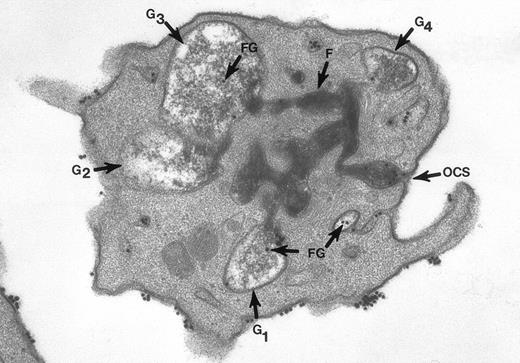

The second experiment also involved human platelets.18,20Cells in suspension were combined with thrombin for 15-second to 5-minute intervals and fixed in solutions containing tannic acid. Tannic acid combines with the surface membrane glycoproteins to form a mordant dye that binds and converts osmic acid to osmium black, an electron dense stain. Tannic acid under these conditions binds only to those membranes exposed to the exterior, or membranes continuous with the outside. Thus, it stains the platelet surfaces and membranes lining channels of the OCS. It has one other desirable feature. Tannic acid also selectively stains fibrinogen and fibrin strands in the same manner as the glycocalyx.20

The surface and OCS membranes are the only structures stained by osmium black in resting platelets. After exposure to thrombin, the dense stain also enters α granules that have become labelized and communicate with the OCS.20 Fibrinogen and fibrin in the process of extrusion from α granules fill channels of the OCS. During this process the OCS becomes dilated, as do the labelized α granules, yielding the appearance of swollen vacuoles (Fig 2). In experiments where the platelets were combined with fibrinogen-coated gold particles before exposure to thrombin and fixation through the tannic acid staining procedure, Fgn/Au was present in OCS channels and in swollen α granules. The findings showed that the OCS is a two-way street, and α granules communicate with channels of the OCS to secrete their contents.

Thin section of a platelet from a sample of washed cells incubated with Fgn/Au particles for 15 minutes, then exposed to 5 U/mL of thrombin for 60 seconds before fixation in glutaraldehyde-tannic acid-osmium to selectively stain the platelet glycocalyx, fibrinogen, and fibrin. This example is one of several serial sections through the same platelet. It and the other serial sections show the typical features of shape change and internal transformation caused by thrombin. Fgn/Au particles are bound to the irregular surface and are in the process of entering channels of the OCS. The OCS channel indicated by an arrow (↑) is filled with fibrinogen and fibrin stained by tannic acid-osmium black. The tortuous channel is connected directly to several granules (G1, G2, G3) in various stages of labelization. Residual fibrinogen is stained by the reaction product. Fgn/Au particles carried by the OCS have entered the granules (G1, G3, G4). The direct connections between OCS channels and granules in this example and its serial sections is indisputable. Original magnification ×45,000. (Reprinted with permission.19)

Thin section of a platelet from a sample of washed cells incubated with Fgn/Au particles for 15 minutes, then exposed to 5 U/mL of thrombin for 60 seconds before fixation in glutaraldehyde-tannic acid-osmium to selectively stain the platelet glycocalyx, fibrinogen, and fibrin. This example is one of several serial sections through the same platelet. It and the other serial sections show the typical features of shape change and internal transformation caused by thrombin. Fgn/Au particles are bound to the irregular surface and are in the process of entering channels of the OCS. The OCS channel indicated by an arrow (↑) is filled with fibrinogen and fibrin stained by tannic acid-osmium black. The tortuous channel is connected directly to several granules (G1, G2, G3) in various stages of labelization. Residual fibrinogen is stained by the reaction product. Fgn/Au particles carried by the OCS have entered the granules (G1, G3, G4). The direct connections between OCS channels and granules in this example and its serial sections is indisputable. Original magnification ×45,000. (Reprinted with permission.19)